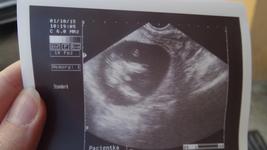

My takhle a mame kluka 🙂

Já vidím pindika ;) ale kdo ví no 😂

Také jsem na prvním screeningu viděla pindíka,pak mě doktorka ,,usadila,, že tipuje více holčičku,že v tomto období ,,to trčí oboum pohlaví,, úplně stejně..Nic méně i nás holčička již po 3. porvzená..

V tomto týdnu mají "pindíka" jak chlapci, tak holčičky. Holkám se během následujících týdnů pomalu zkracuje a vznikne z něj klitoris, chlapcům se vytvaruje penis.

V tomhle stádiu těhotenství se pohlaví určuje podle sklonu pohlavního hrbolku, ale to se nejlépe určuje z fotek, kde je dítě zabrané z profilu. Takhle ti nikdo nic neřekne. 🙂

Ve 13/14tt vypadá pohlaví skoro stejně, záleží na ose nějakého náklonu (popisuju to šíleně, omlouvám se, ale tak jsem to pochopila já na screeningu) a rozeznat holku nebo kluka dokáže opravdový odborník